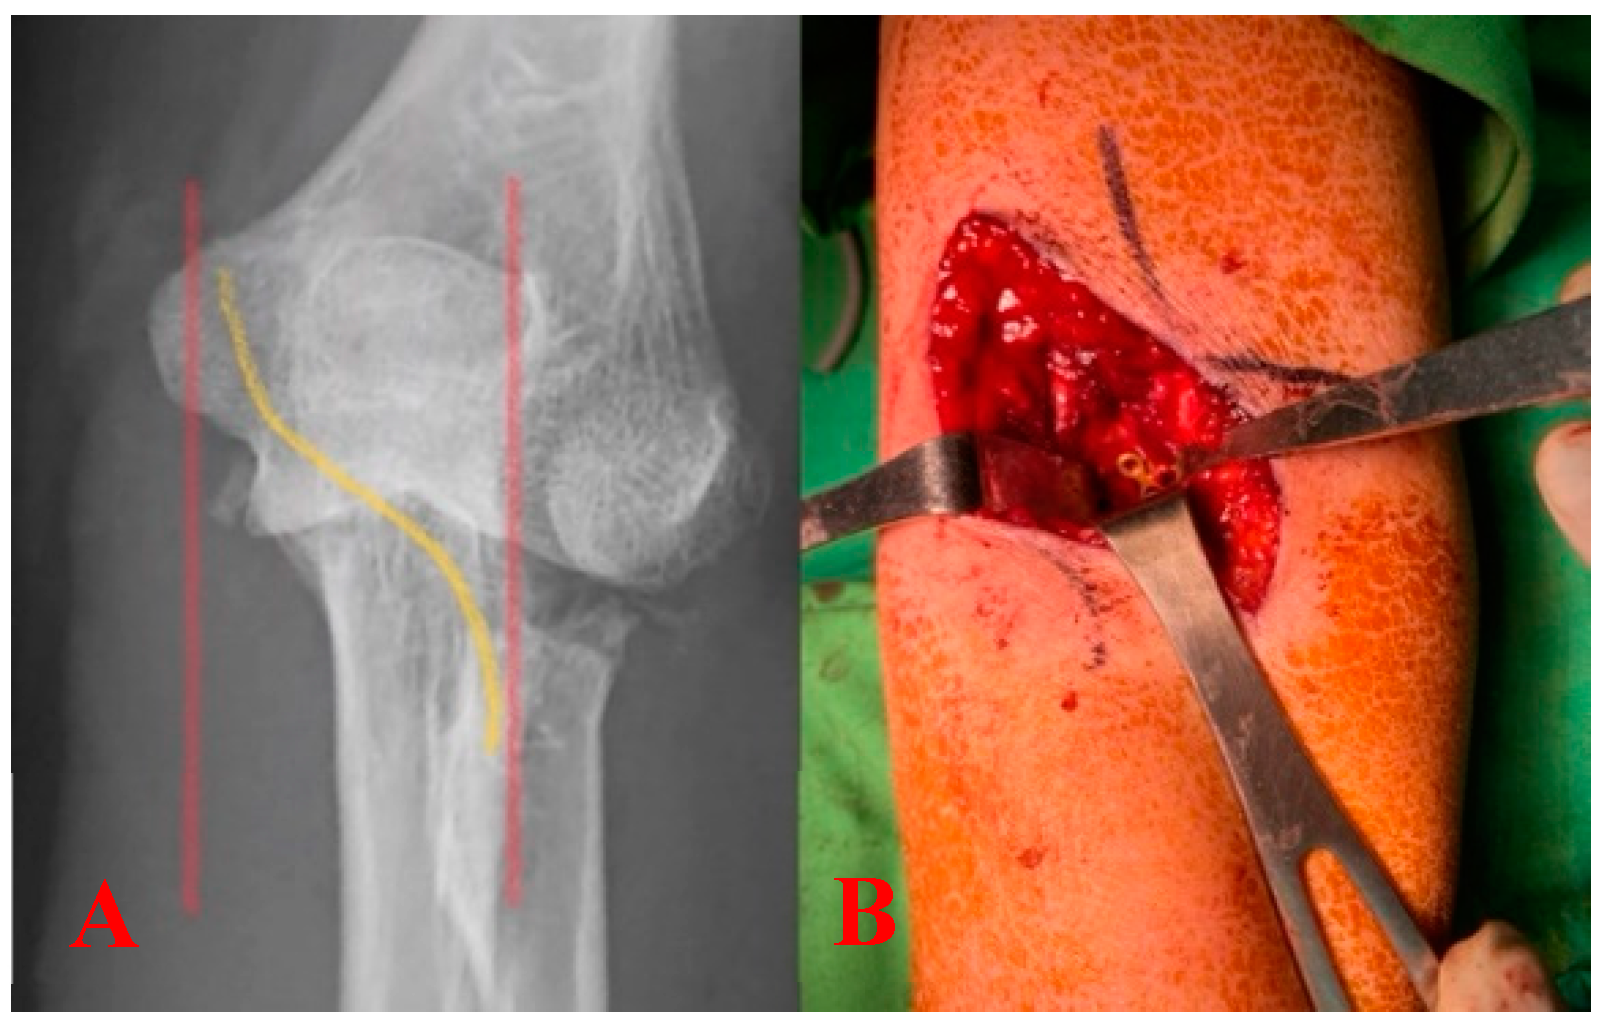

2.2. Steps of Fixing Coronoid Process Anteriorly

2.3. Fixation of Radial Head